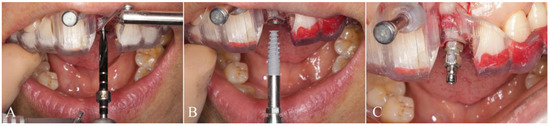

2.4. Surgical Procedure